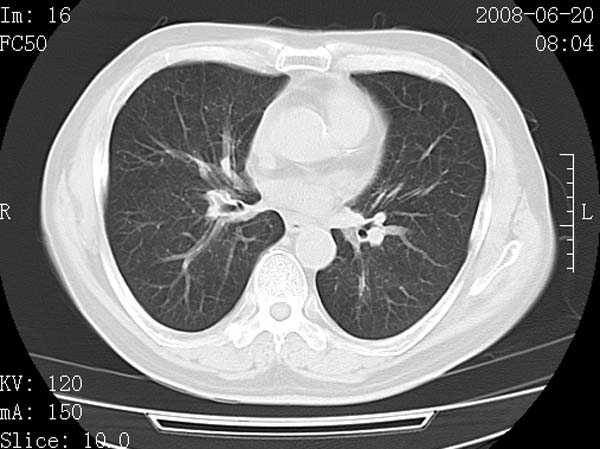

以下是引用守望可可西里在2008-6-24 1:11:00的发言:[br][br] 考虑为周围型肺癌:[br] 1.分叶结节,形态极不规则,蟹足样伸展的恶性浸润特征比较明确。[br] 2.磨玻璃影中由多个更高密度小结节聚集呈梅花瓣样。[br] 3.局部胸膜凹陷征比较明确。[br][br] 另:纵隔胸膜明显增厚、粘连。

以下是引用zjzjr在2008-6-24 11:19:00的发言:[br]支持左下肺周围型肺癌伴右肺转移,纵隔淋巴结转移,心包积液.

以下是引用zhangling在2008-6-24 14:56:00的发言:[br]我们科室意见报告为[br][br]1考虑左下肺周围型肺癌[br]2右肺小结节考虑转移瘤,纵隔淋巴结转移[br]3心包积液. [br] 各位老师分析的相当好 谢意[br]